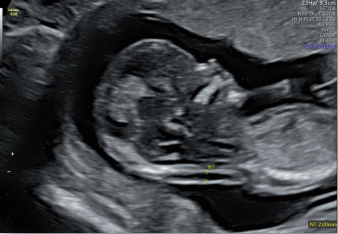

據(jù)官方統(tǒng)計,我國孕婦產(chǎn)檢率達(dá)到97.4%,由于診療量大、檢測時間長、流程復(fù)雜等問題,導(dǎo)致醫(yī)生工作量極大;大家都希望能有一臺更高效智能機(jī)器,解決產(chǎn)科超聲的臨床痛點。

在合適切面下,可自動識別測量臨床所需的胎兒雙頂徑,頭圍,腹圍,股骨長和肱骨長度等多個參數(shù)。

胎兒頸后透明層/顱內(nèi)透明層標(biāo)準(zhǔn)化測量,減少主觀因素差異。

適用場景:Voluson S6不僅強(qiáng)在婦產(chǎn),它豐富的探頭群和全面的應(yīng)用功能也可以同時兼顧新生兒、兒科、成人全身檢查等,提供一站式的超聲檢查解決方案。